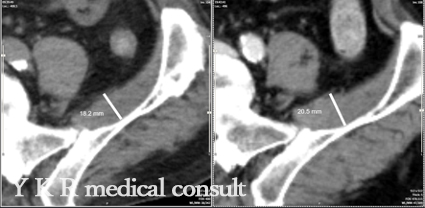

動脈瘤の見落としにおける準備書面のコンサルティングについて1 依頼内容ContentMRI画像内に動脈瘤が存在したにもかかわらず、これが見逃されたため、患者の動脈瘤が破裂したことによりくも膜下出血が発生した。医療過誤の認 […]